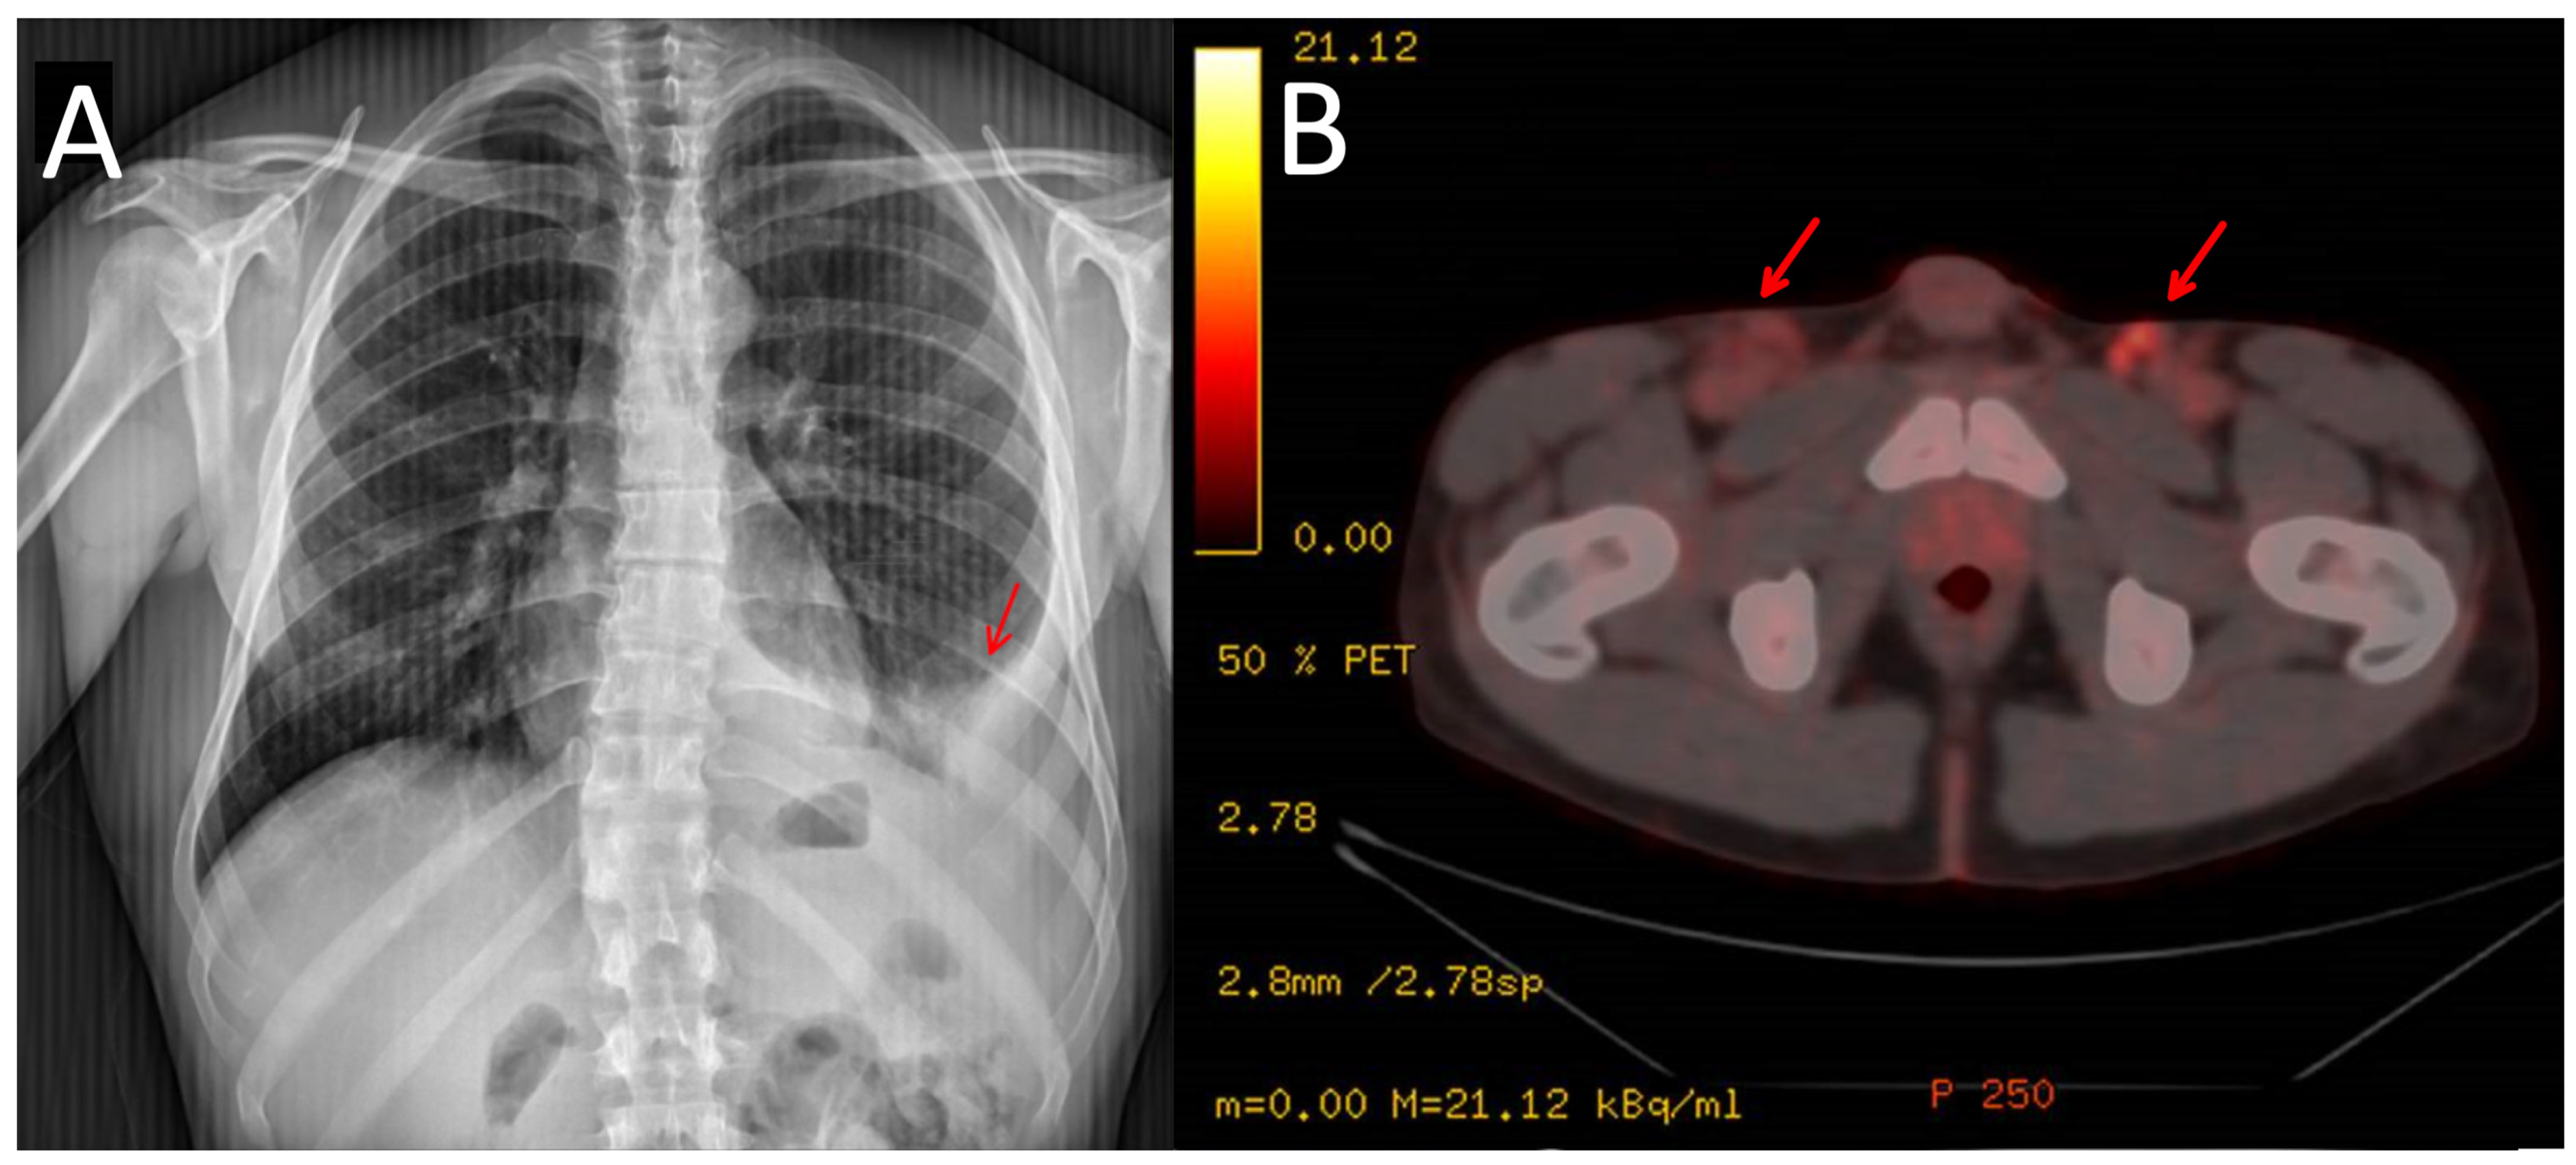

2. Case Presentation